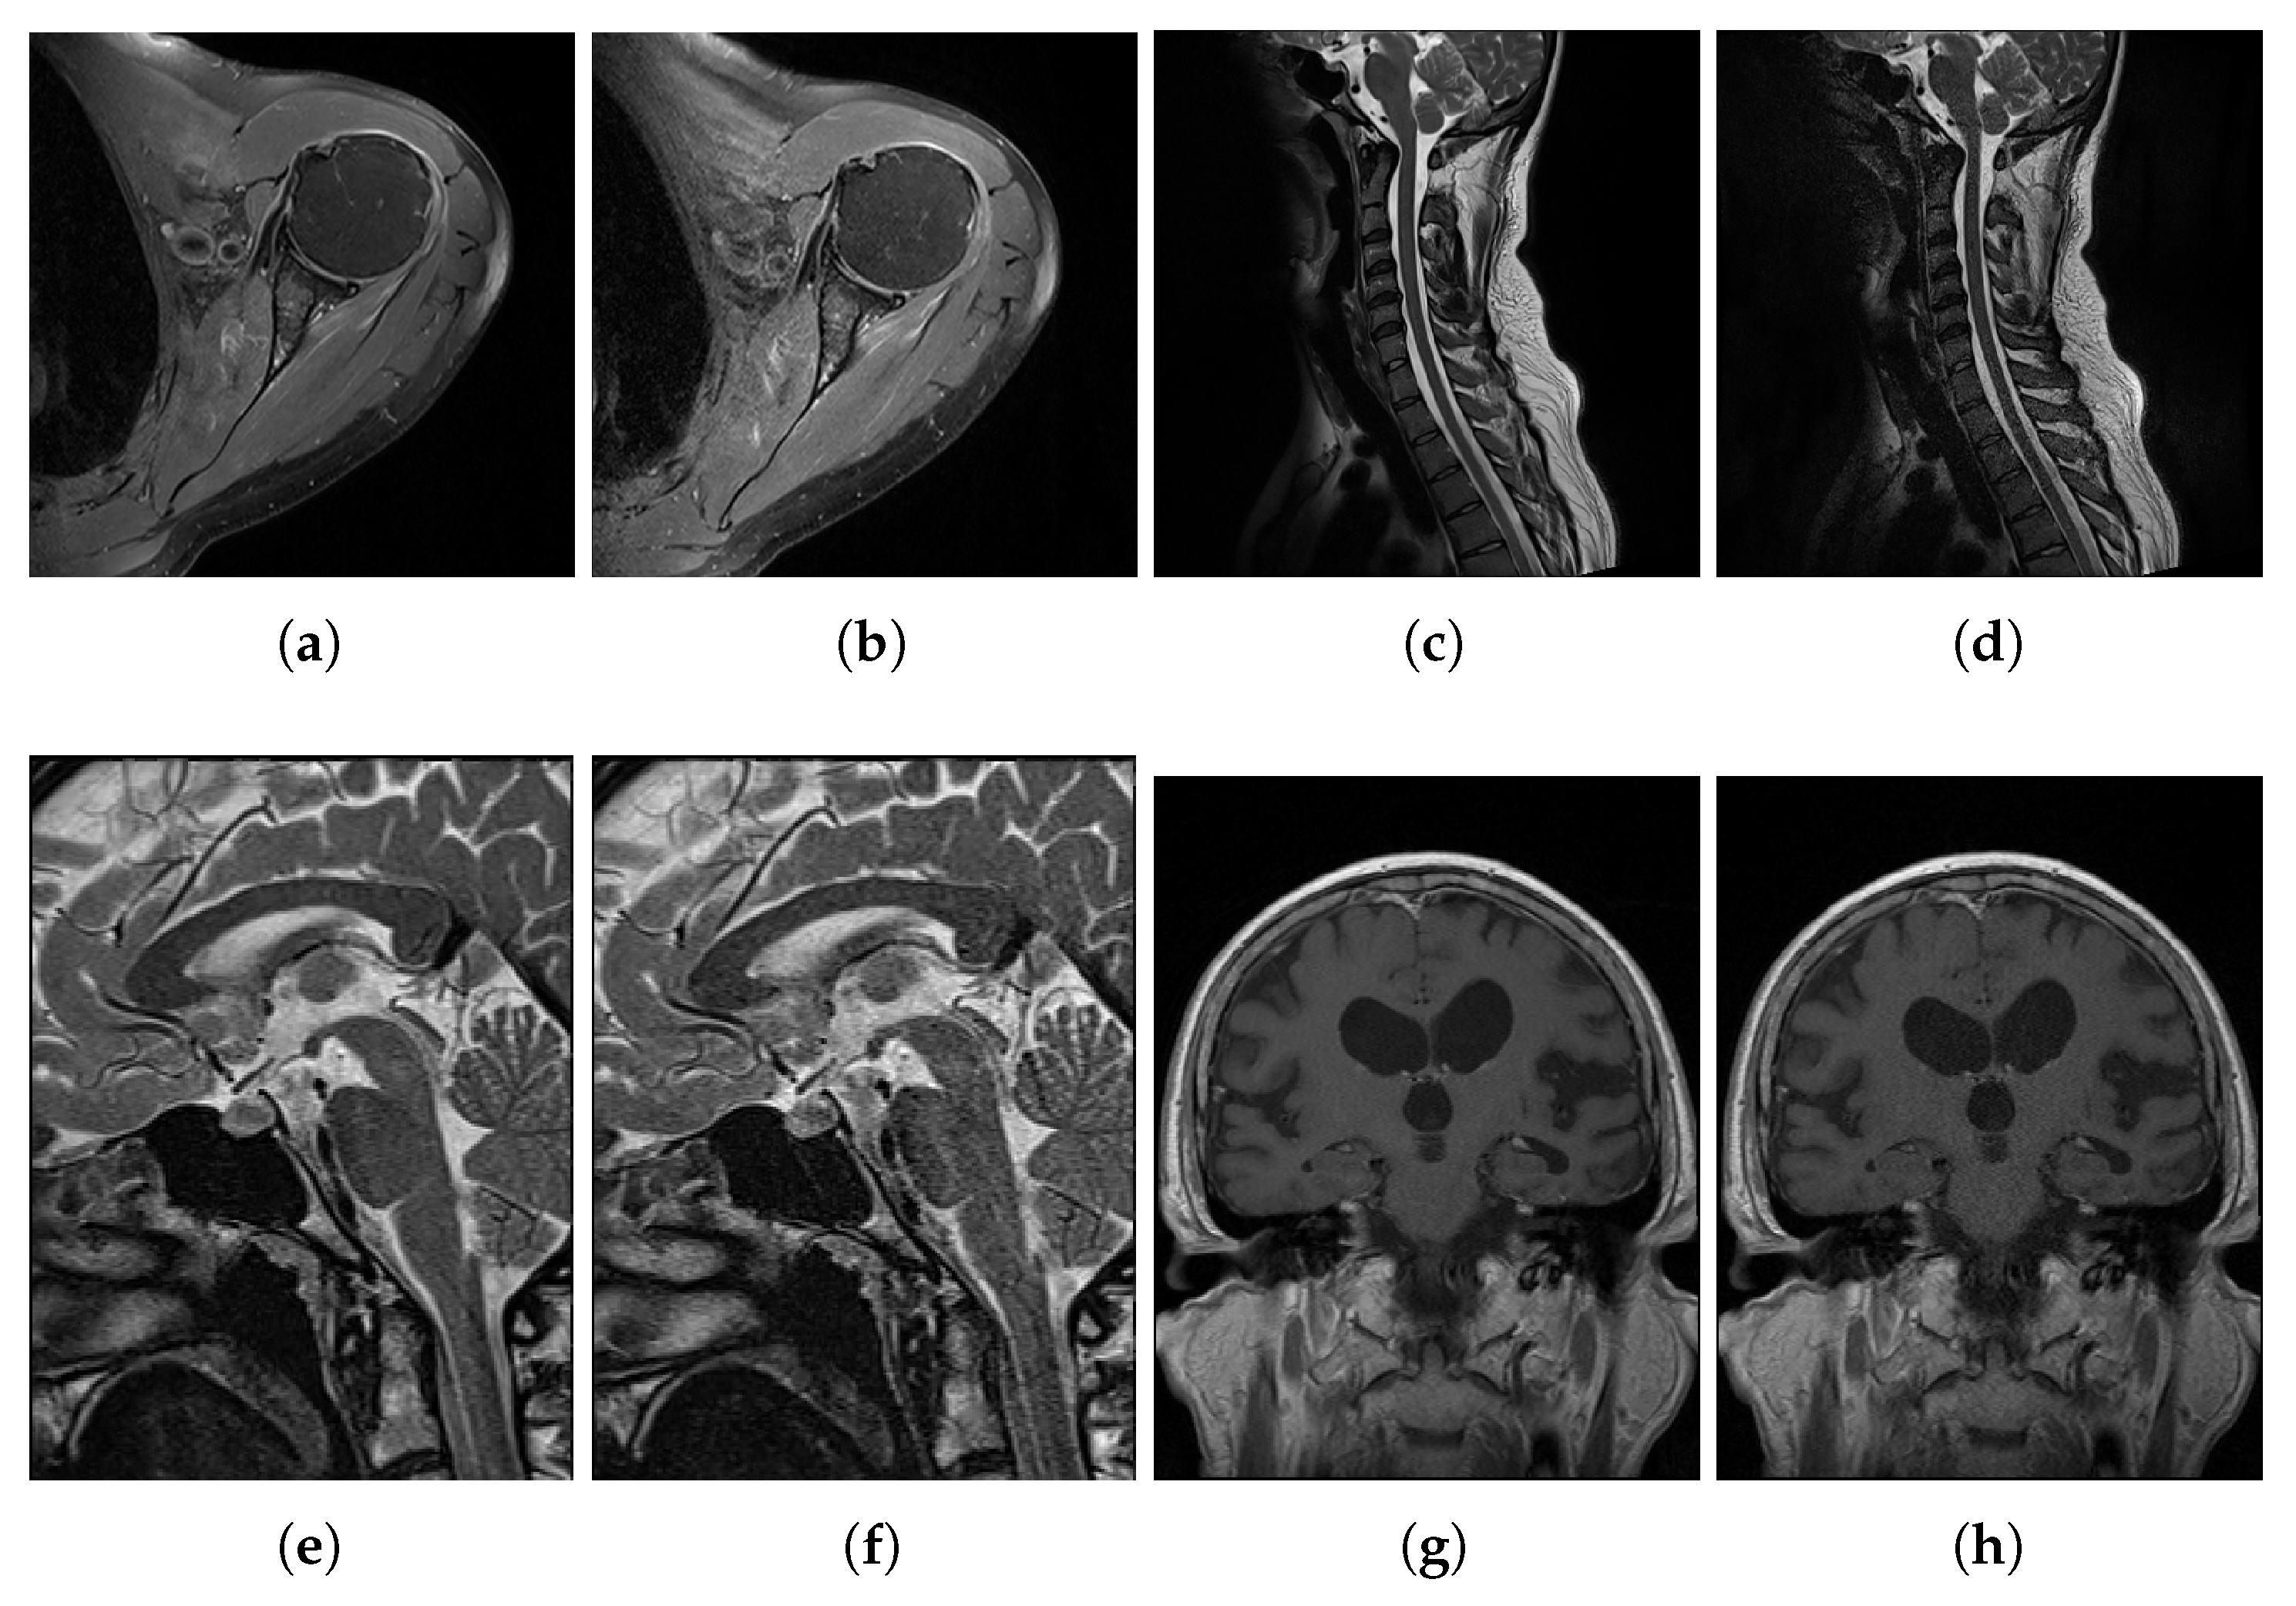

3.1. Experimental Data

| Body Part | No. of Image Pairs | Axial Plane | Sagittal Plane | Coronal Plane |

|---|---|---|---|---|

| Lumbar and cervical spine | 7 | 2 | 5 | 0 |

| Knee | 7 | 2 | 4 | 1 |

| Shoulder | 8 | 2 | 2 | 4 |

| Wrist | 3 | 0 | 0 | 3 |

| Hip | 2 | 1 | 1 | 0 |

| Pelvis | 2 | 0 | 0 | 2 |

| Elbow | 1 | 1 | 0 | 0 |

| Ankle | 1 | 0 | 1 | 0 |

| Brain | 4 | 1 | 2 | 1 |

| Total pairs | 35 | 9 | 15 | 11 |